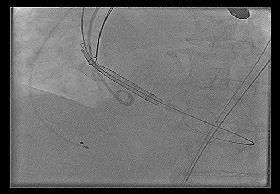

◆2015年1月17日行TAVI术。

◆植入29mm CoreValve人工支架瓣膜一枚。

术后症状明显缓解,近一年未因心衰住院;

一年期复查心超,未见主动脉瓣狭窄和关闭不全。